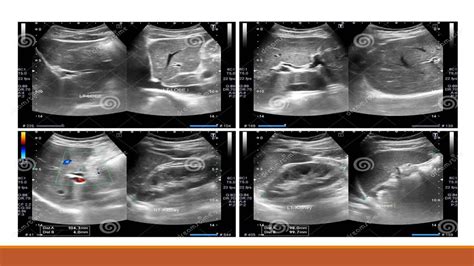

An ultrasound of abdomen is used to evaluate a wide range of conditions affecting the abdominal organs. Some of the most common uses include:

• Kidneys: Examining the kidneys for stones, tumors, cysts, or other abnormalities.

Interpreting the Results of an Ultrasound of Abdomen

The images obtained from an ultrasound of abdomen are reviewed by a radiologist, who provides a detailed report to the referring physician. The results can help diagnose various conditions, including:

• Kidney Stones: The location and size of kidney stones can be determined.